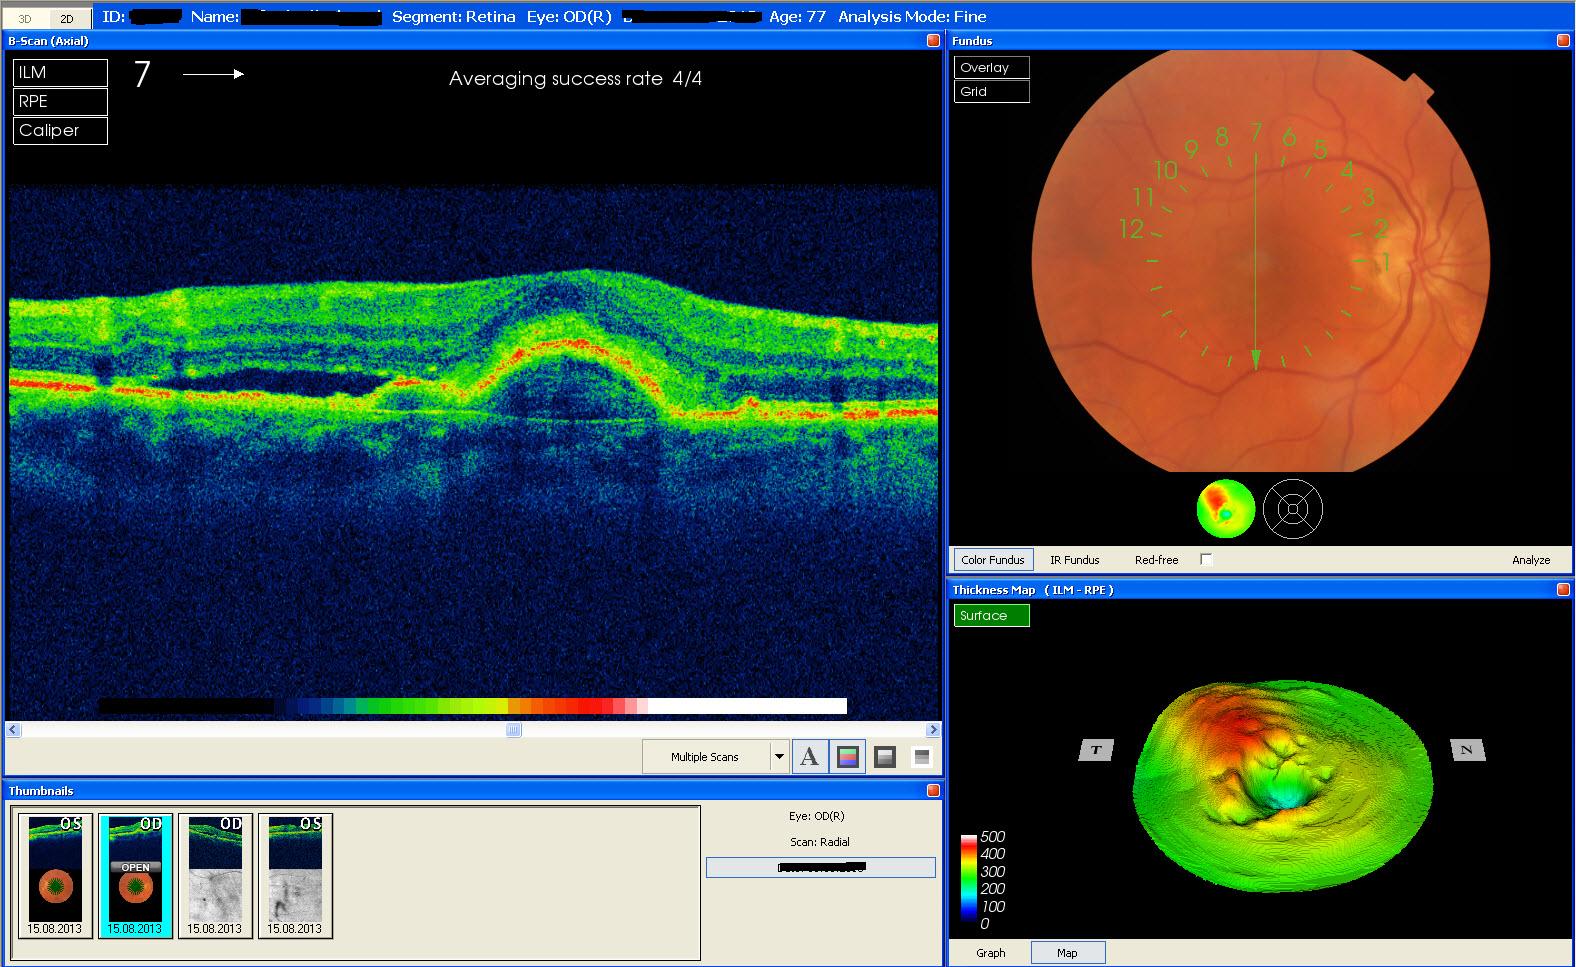

Bei Patienten mit Makula- oder Netzhauterkrankungen (z.B. bei Diabetes oder Makuladegeneration) kann es neben einer Stoffwechselstörung zu einer Flüssigkeitseinlagerung in die Netzhaut kommen. Eine sehr genaue, nicht invasive Methode, die Menge der Flüssigkeit und die genaue Lokalisation zu messen, ist die Optische Kohärenztomographie.

Die innere Struktur der mehrschichtigen Netzhaut im am Augenhintergrund kann mit den herkömmlichen Verfahren nicht genau untersucht werden. Durch die OCT-Technik ist dies heutzutage in einer kurzen Untersuchungszeit völlig unschädlich, ohne Strahlenbelastung und ohne Berührung des Auges möglich. Durch die OCT-Untersuchung gelingt eine exakte Darstellung der verschiedenen Schichten der Netzhaut und damit eröffnet sich eine neue Dimension der Diagnostik und Verlaufskontrolle bei verschiedenen Netzhauterkrankungen.